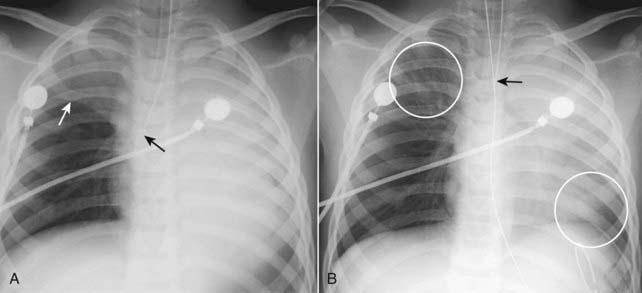

image

Figure 5-4 Atelectasis of the right lung.

There is complete opacification of the right hemithorax with shift of the trachea (solid black arrow) toward the side of the atelectasis. The left heart border is displaced far to the right and now almost overlaps the spine (solid white arrow). This patient had an endobronchial metastasis in the right main bronchus from her left-sided breast cancer. Did you notice the left breast was surgically absent?

image Endotracheal tube too low (Fig. 5-13)

If the tip of an endotracheal tube enters the right lower lobe bronchus, only the right lower lobe tends to be aerated and remain expanded. Within a short time, atelectasis of the entire left lung and the right upper and middle lobes will develop.

Once the tip of the endotracheal tube is withdrawn above the carina, the atelectasis usually clears quite rapidly.

Figure 5-13 Right upper lobe and left lung atelectasis from an endotracheal tube.

A, The tip of the endotracheal tube extends beyond the carina into the bronchus intermedius (solid black arrow), which aerates only the right middle and lower lobes. The right upper lobe and entire left lung are opaque from atelectasis. The minor fissure is elevated (solid white arrow). B, One hour later, the tip of the endotracheal tube has been retracted above the carina (solid black arrow) and the right upper lobe and a portion of the left lower lobe are again aerated (white circles).